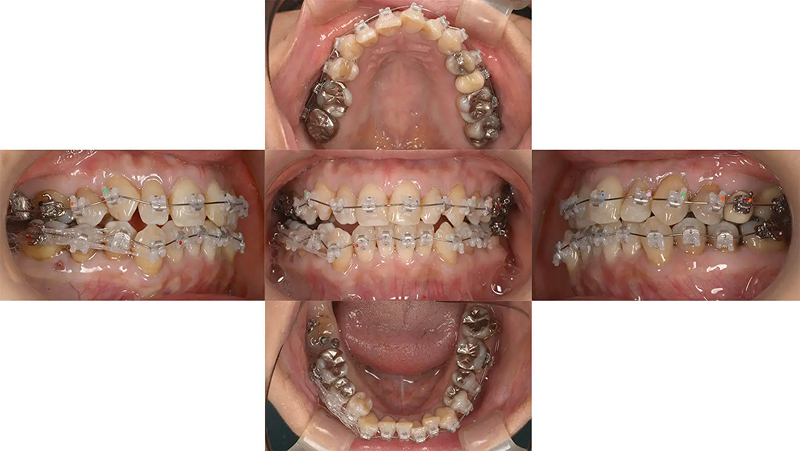

Case01右側奥歯が噛んでいない状態を親知らずを利用し改善した症例

右下第2大臼歯が親知らずの影響で予後不良の状態でした。第2大臼歯を抜歯して、矯正治療で親知らずを利用できないか相談にいらっしゃいました。右側奥歯は交差咬合でしっかり噛めていない状態でした。診査の結果、矯正用アンカーを用いた矯正治療で改善すると診断しました。親知らずは予定通り、第2大臼歯の位置に移動でき、抜歯の跡を隠すことができました。

初診 2016.5.13

矯正開始 2017.6.21

ファイナル 2018.9.4

| 主訴 | 右側奥歯が噛んでいない、親知らずを利用できないか |

|---|---|

| 診断 | 両側アングル1級の叢生 |

| 矯正方法 | 矯正用アンカーを用いたマルチブラケット |

| 矯正期間 | 15か月・17回 |

| 費用 | 730,000円(税別) |

| 調整料 | 月1回 5,000円(税別) |